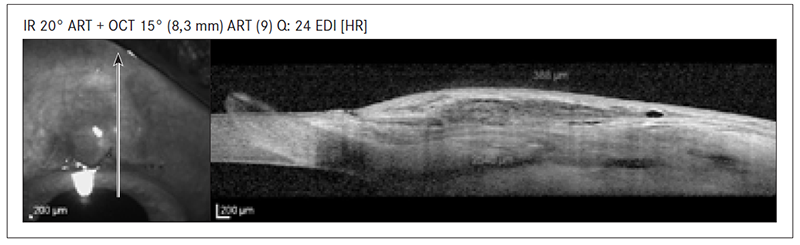

- iekapsulējies filtrācijas spilventiņš – bieza sieniņa, viena milzīga subkonjunktivāla telpa, augstas intensitātes signāls subkonjunktivāli (sk. 3. att.);

3. attēls. Iekapsulējies filtrācijas spilventiņš / Encapsulated filtration bleb